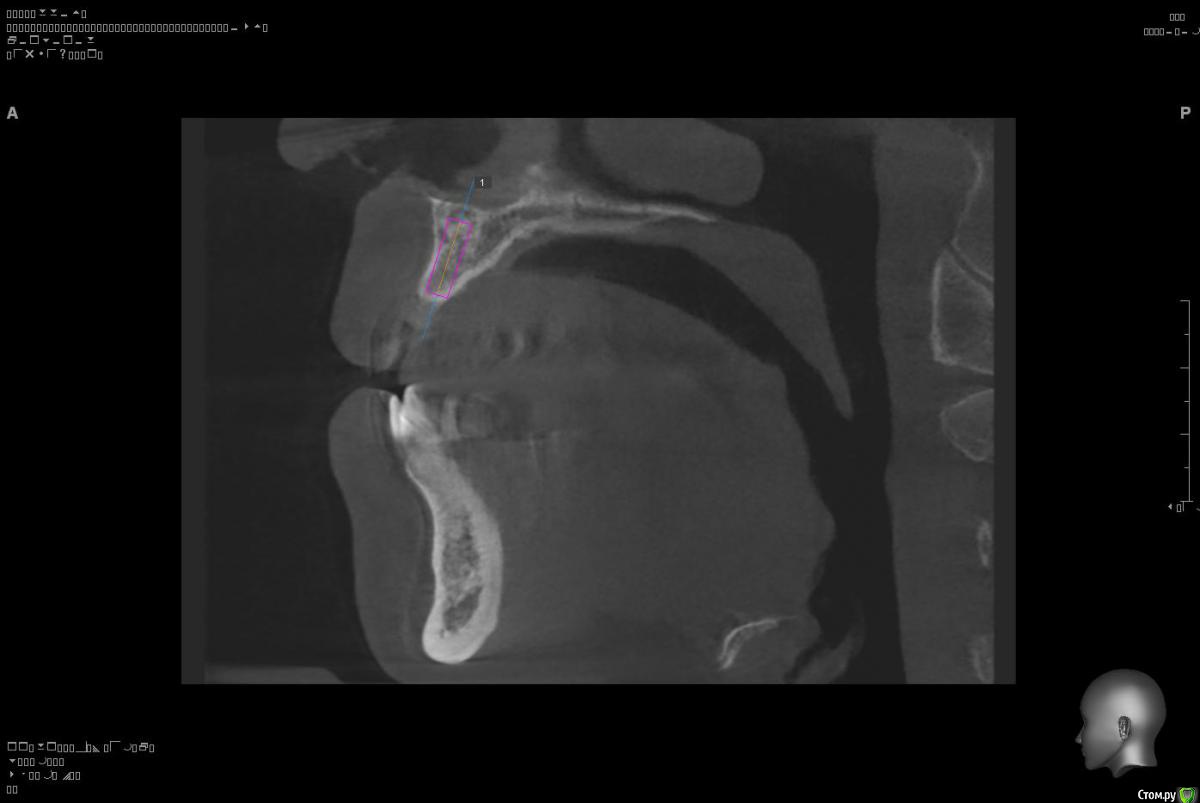

Platon Опубликовано 10 января, 2016 Поделиться Опубликовано 10 января, 2016 Здравствуйте.Помогите с планированием начинающему.Пациентка 38 лет. отсутствует 21. визуально в области 21 провал (фото нет, пока только кт). ходит с акриловой "птичкой"ортопед говорит: ставь, она к эстетике не будет предъявлять претензий))). с чем мне не хочется соглашаться(система ALPHA BIOкак правильно поступить?какие варианты рассматриваю:1. имплантация 3,75 на 11.5 SPI. ,+ временная коронка. Без какой либо пластики.2. костная пластика (мембрана,ксено,) без имплантации, сст, капа на 4 -6мес. потом имплантация + временная коронка3. имплантация, сст , временная коронка С учетом обстановки, прессинга, отсутствия опыта в аугментации, склоняюсь к третьему варианту. заранее спасибо за советы!удачного дня! Ссылка на комментарий

Platon Опубликовано 31 января, 2016 Автор Поделиться Опубликовано 31 января, 2016 Продолжение.не судите строго за фото, первый раз вообще фоткаю операцию)спасибо за советы.По порядку. После того, что мне написали, я решил все -таки уговорить на конусный имплантат (3.7-11.5 ImplantDirect). Также ортопед не хотел делать временную коронку, сказал что сделает каппу, птичку в топку -тоже сделали. Слизистая в области 21 была в рубцах. Исходя из этого всего я решил, коль временной коронки не будет, то сст подсаживать тоже не стану пока,(ортопеда уговаривал сделать временную коронку)))- торк был хороший 35-50н) для того чтобы сст попрактиковаться, но(((.в итоге, анестезия, разрез, сверло пилотное и сверло 2.2, далее расщепление с помощью набора майзенгер с использованием спредеров до нужного диаметра, установил имплантат, торк контролируемый, можно было подобрать любой) в итоге оставил 35. заглушка, совсем немного ксено, мембрана, ушился. ждем. Будет что-то типо каппы которая слегка отдавливает десну,формируя сосочки. не знаю, ни разу такую еще не видел.планирую на этапе раскрытия все-таки сст и временную коронку увидеть.вот. через 4 мес. выложу, что получилось) Если есть советы, критика, всему буду рад, спасибо 3 Ссылка на комментарий

St_Klaus Опубликовано 1 февраля, 2016 Поделиться Опубликовано 1 февраля, 2016 взять 11,5 не заглублять данный имплант, оставить 1,5 мм супракрестально., если позволяет десна, чтобы уменьшить ремоделинг кости. Соглашусь, альфа не предназначена для заглубления, если не ошибаюсь, даже производители не рекомендуют.Если есть советы, критика, всему буду рад, спасибоВсе хорошо, только чуть более небно бы вывел платформу, хотя бы 0,5 мм Ссылка на комментарий